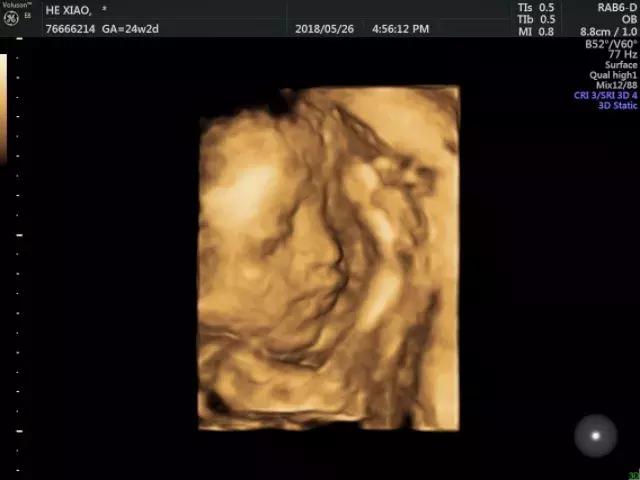

现在,你还在你妈妈肚子里,图片中是5月份做四维B超的你,这是我第一见到你的模样,说实话把我吓了一跳,真的好丑,比爸爸还丑,哈哈。说这话的时候你妈妈在旁边揪了爸爸一下。在这里想对你说的是:爸爸也是初为人父,今后还请你多关照!然后咱们一起学习、一起成长,做一个对社会有贡献的人!

杭州石油 熊刚